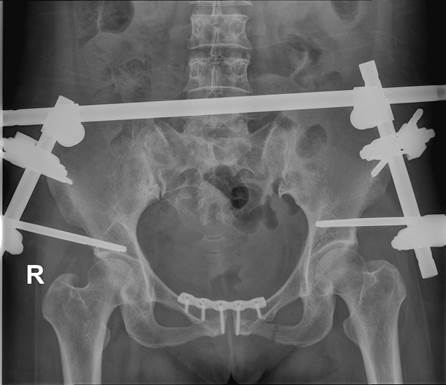

病例二:Tile C1分型,术前X线

病例二:Tile C1分型,术后复查X线